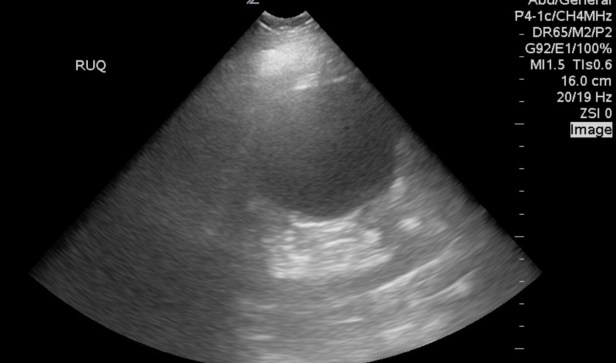

When evaluating a patient with right upper quadrant pain the trainee found the below structure and became immediatly terrifed she came across an abdominal aortic aneurysm. As a resident myself I had a terrifying case where the patient came in with right upper quadrant pain and my POCUS revealed a ruptured AAA. However, in this case it was the classic fake out renal cyst. As we scanned further, fanned through in two planes it became clear this structure originated from the kidney. Also, the aorta next door was a normal diameter….